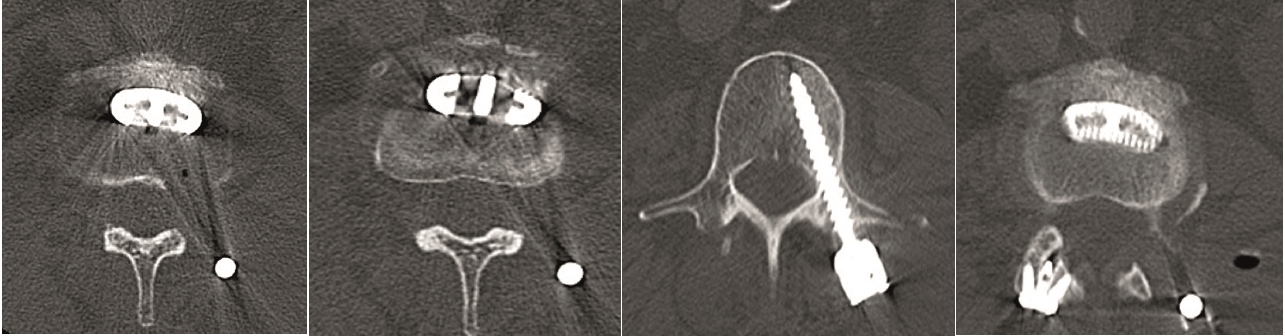

The Facet Wedge spine system includes the following implants and features (Fig 5):

Kirschner wire hole enables guided insertion over K-wire (a)

Rails stop translational motion and generate contact between subchondral bone and implant (a)

Low profile feature decreases muscle irritation (b)

Implant shoulder that controls insertion depth (b)

Teeth keep the implant in the desired position prior to screw insertion (b)

Divergent angular stable locking screws for primary fixation (b)

Various implant sizes to accommodate patient anatomy (b)

Perforations create optimal fusion conditions (c).